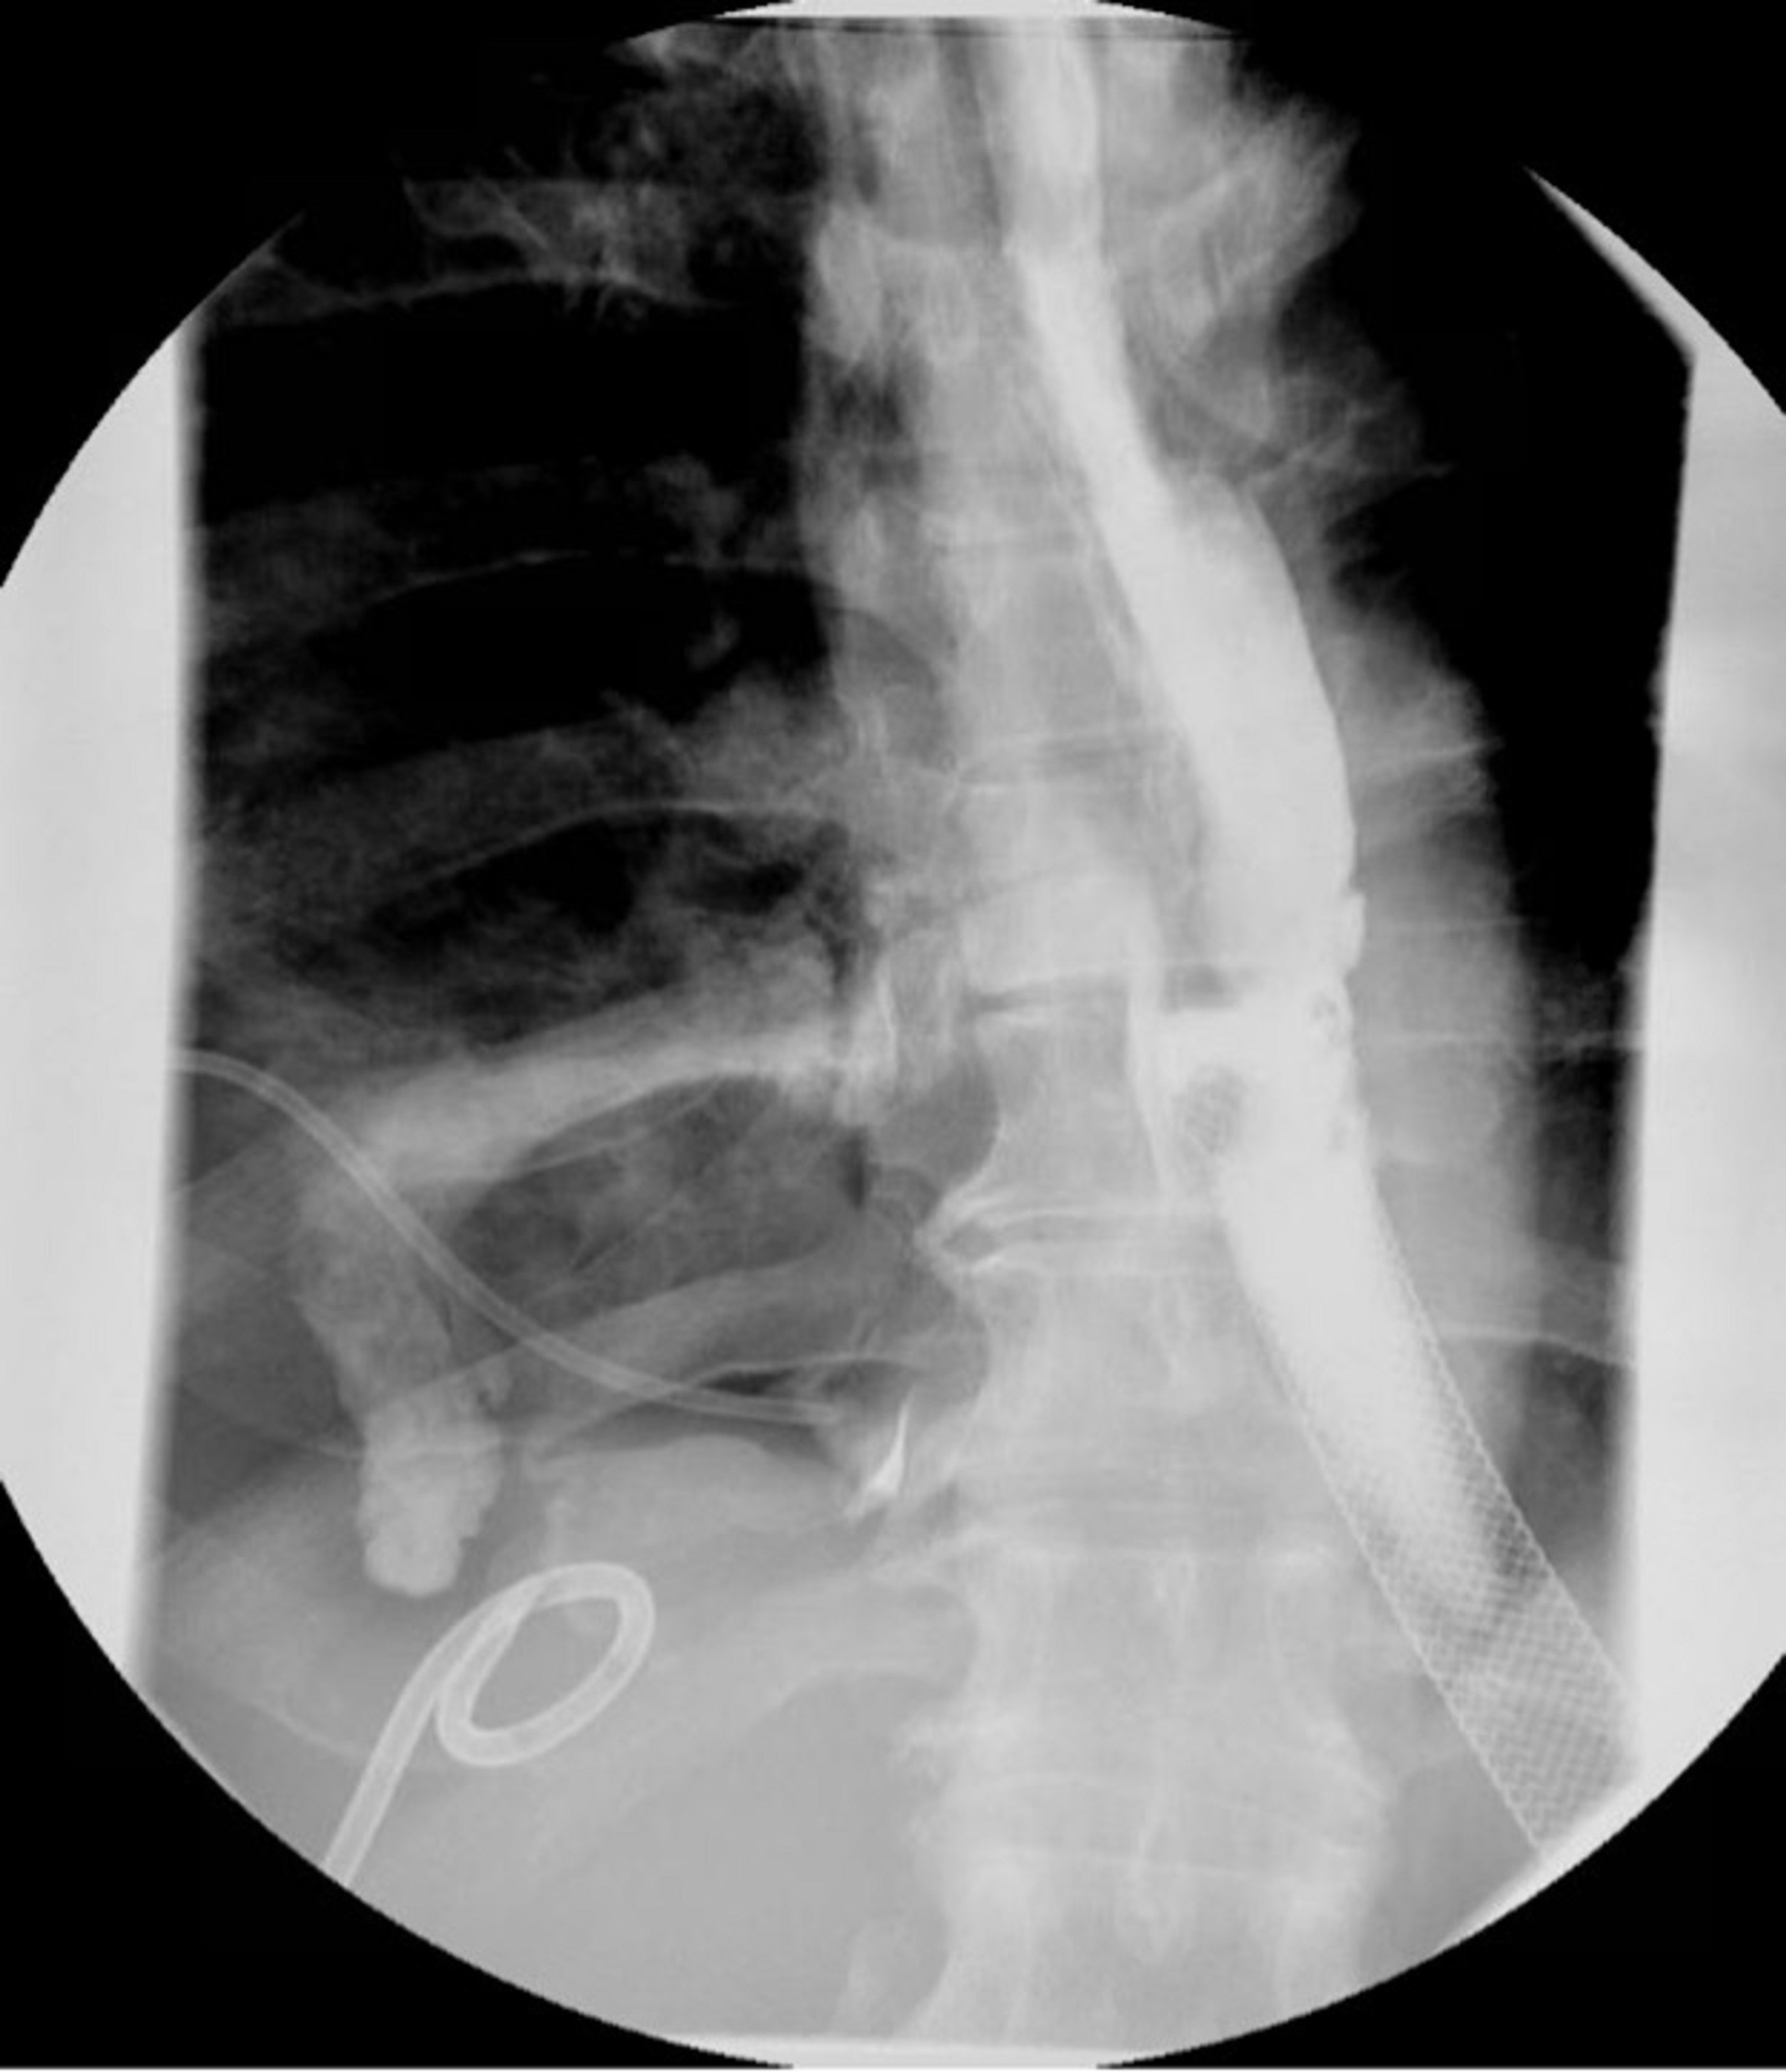

Esophageal Stent X Ray

a Esophageal stent inserted over the guidewire under fluoroscopic Chest Pain Esophageal Stent This can be managed by endoscopic. In the past, the use of stents has been limited by patient complaints of chest pain and globus sensation, as well as complications such as. You might have pain when you swallow or feel like food is getting stuck in your chest. Complications associated with esophageal stents are generally classified as either early or. Chest Pain Esophageal Stent.

Fluoroscopic image of an esophageal stent sutured in place in a patient Chest Pain Esophageal Stent This makes it difficult to swallow. In different studies, it was present in even 100% of. Cancer in the food pipe (oesophagus) can partly or completely block it. Esophageal stents are widely used to treat a variety of problems, most commonly malignant dysphagia. Complications associated with esophageal stents are generally classified as either early or delayed. The food might come. Chest Pain Esophageal Stent.